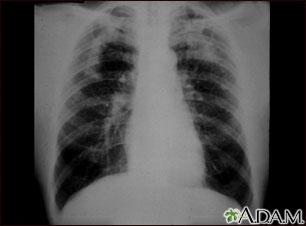

This picture shows complicated coal workers pneumoconiosis. There are diffuse, small, light areas (3 to 5 mm) in all areas on both sides of the lungs. There are large light areas which run together with poorly defined borders in the upper areas on both sides of the lungs. Diseases which may explain these X-ray findings include complicated coal workers pneumoconiosis (CWP), silico-tuberculosis, disseminated tuberculosis, metastatic lung cancer, and other diffuse infiltrative pulmonary diseases.